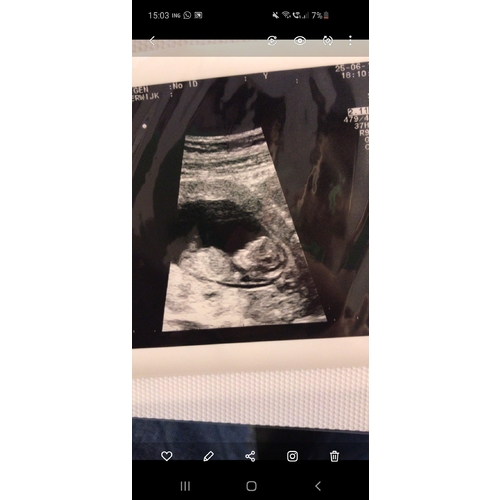

Ja, maar ze kon sowieso geen goede fotos meegeven en 3d lukte zelfs niet.

Voor 3D is het vruchtje dan ook nog te klein... Het is amper een paar centimeter groot én in volle ontwikkeling. Helemaal niks raar aan de hoofdvorm, en allesbehalve een reden om je zorgen over te maken.